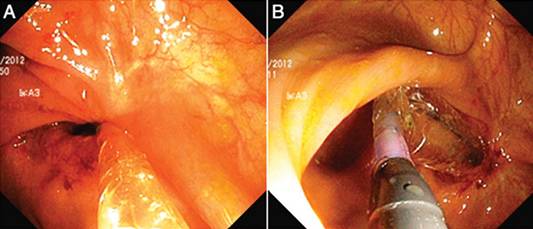

图7. 狭窄的治疗: 球囊扩张及针刀狭窄切开术。 (A 和B) 球囊扩张造成的深度撕裂- 较难控制深度及部位。 (C 和D) 针刀治疗前后对比- 深度和部位均在可控范围之内。

狭窄及瘘管是克罗恩病(CD)的常见并发症,CD狭窄的主要内镜治疗方式是球囊扩张和针刀狭窄切开术,CD相关性瘘管的内镜治疗方式包括局部注射、内镜夹瘘管闭合术及瘘管切开术。

CD的针刀治疗

1.内镜针刀成形术

针刀狭窄切开术可用于回结肠狭窄、回肠J型储袋狭窄和Kock储袋狭窄的治疗,我们认为针刀较EBD治疗CD或非CD狭窄均更有优势,主要表现在治疗后复发率低。针刀治疗虽然在有经验的内镜医生手中能确保一定的安全性,但它较之于EBD创伤更大(表2),因此一般用于EBD治疗后复发的纤维性狭窄。